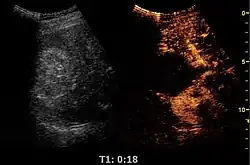

Contrast-enhanced ultrasound (CEUS) is the application of ultrasound contrast medium to traditional medical sonography. Ultrasound contrast agents rely on the different ways in which sound waves are reflected from interfaces between substances. This may be the surface of a small air bubble or a more complex structure. Commercially available contrast media are gas-filled microbubbles that are administered intravenously to the systemic circulation. Microbubbles have a high degree of echogenicity (the ability of an object to reflect ultrasound waves). There is a great difference in echogenicity between the gas in the microbubbles and the soft tissue surroundings of the body. Thus, ultrasonic imaging using microbubble contrast agents enhances the ultrasound backscatter, (reflection) of the ultrasound waves, to produce a sonogram with increased contrast due to the high echogenicity difference. Contrast-enhanced ultrasound can be used to image blood perfusion in organs, measure blood flow rate in the heart and other organs, and for other applications.

Untargeted microbubbles, such as the aforementioned SonoVue, Optison, or Levovist, are injected intravenously into the systemic circulation in a small bolus. The microbubbles will remain in the systemic circulation for a certain period of time. During that time, ultrasound waves are directed on the area of interest. When microbubbles in the blood flow past the imaging window, the microbubbles' compressible gas cores oscillate in response to the high frequency sonic energy field, as described in the ultrasound article. The microbubbles reflect a unique echo that stands in stark contrast to the surrounding tissue due to the orders of magnitude mismatch between microbubble and tissue echogenicity. The ultrasound system converts the strong echogenicity into a contrast-enhanced image of the area of interest. In this way, the bloodstream's echo is enhanced, thus allowing the clinician to distinguish blood from surrounding tissues.